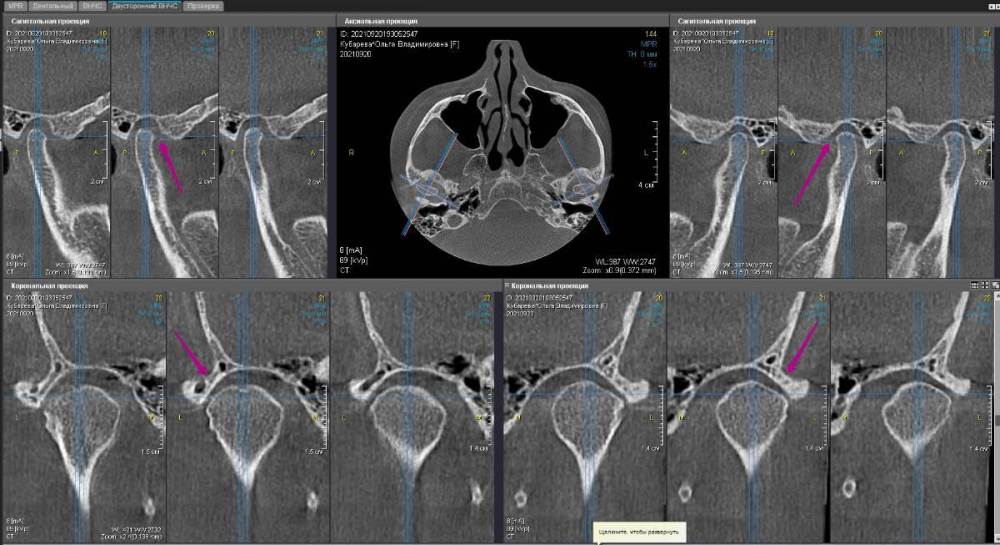

До:

Закончил тотал и решил поделиться. Протезировали с учетом положения ВНЧС в концепции Славичека.  В конце изготовление брукс чекеров для проверки нежелательных контактов во время сна.  Гигиену пытаемся победить...